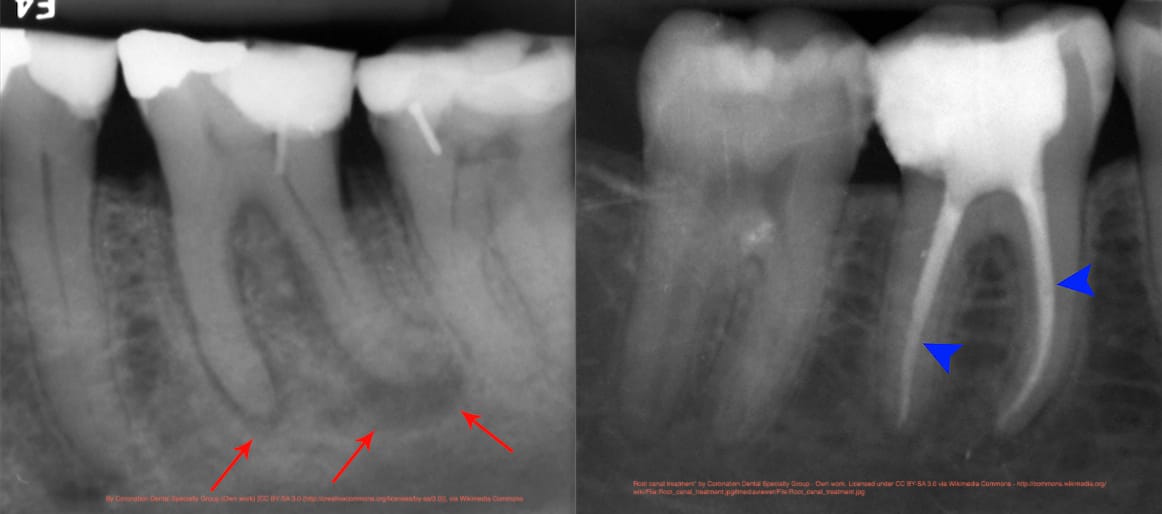

A tooth’s outer portion or Crown consists of a three-layered structure, including Enamel, Dentin, & Pulp. If the tooth decay is limited to the first two layers, it can be corrected with Filling or Restoration. In case the tooth decay reaches the third layer and causes inflammation or infection of the pulp, a Root Canal Treatment (RCT) is needed.

- Root Canal Treatment (RCT) or Endodontic Treatment, is a dental procedure done when tooth decay reaches the pulp (innermost layer of the tooth), causing inflammation. It is necessary to save the damaged tooth to prevent extraction. An endodontist (Root Canal specialist) performs this procedure. The procedure involves.

Removal of inflamed or infected Tooth Material. - Cleaning and disinfection.

- Fill and seal with an inert material.

Root Canal Treatment becomes necessary when tooth decay progresses to the point where it reaches the pulp. The decayed portion of the tooth is removed, and the canal is cleaned and sealed to prevent further infection.